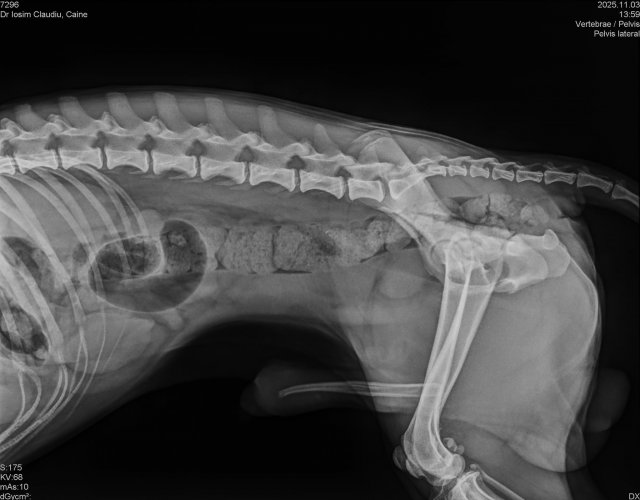

Caine accidentat

O doamna a gasit un caine lovit de masina si l-a tras pe marginea drumului pentru a suna peste tot in cautare de ajutor. Am raspuns pozitiv si am facut totul pentru el. Din pacate nu a putut fi salvat, decedand a doua zi dupa interventia chirurgicala. Foarte probabil din cauza unei embolii pulmonare. Le multumim celor care au donat. Medicul a anulat factura iar banii vor ajuta desigur alte animale de care ne ocupam zilnic.